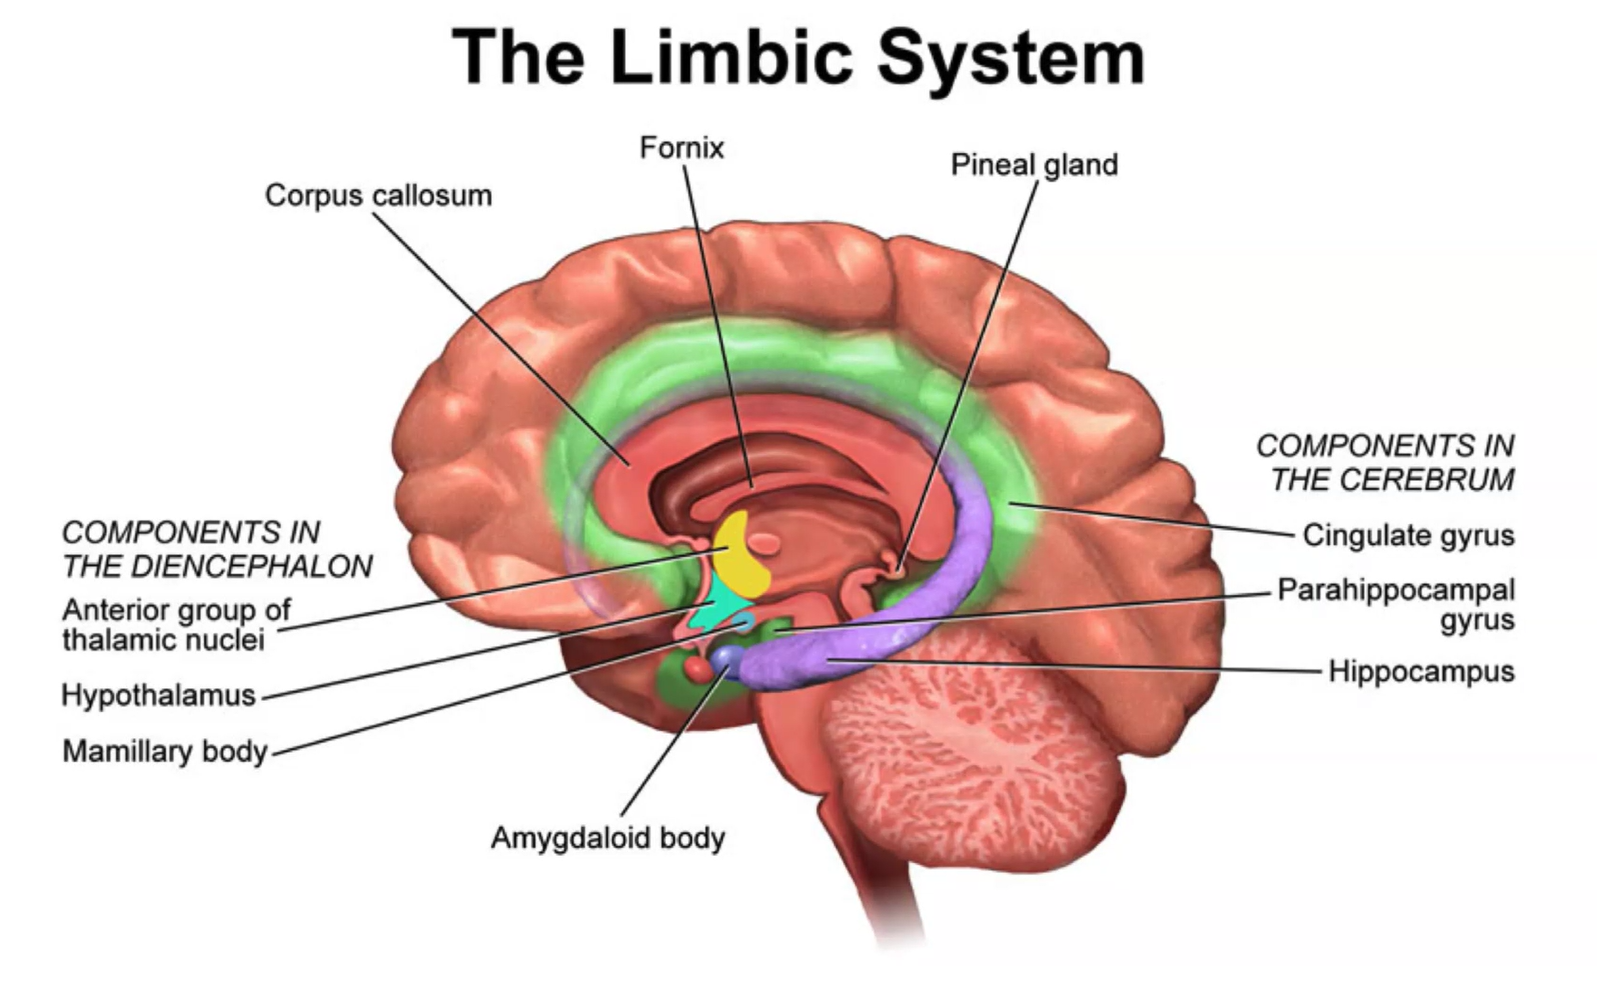

Limbic System

Parts of the Limbic System

Where can we find mamillary bodies

posterior to optic chiasm

The limbic system (flowchart)

Limbic system, alternative visualization